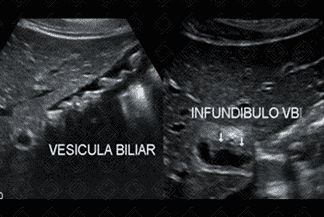

Texto alternativo para a imagem Figuras 1 e 2. Créditos: Dra. Elazir Mota - Rio de Janeiro/RJ

Descrição das figuras 1 e 2: Ultrassonografia de abdome. Imagens ecogênicas, com sombra acústica posterior, móveis durante a mudança de decúbito, sem fluxo ao Doppler colorido, compatíveis com cálculos no interior da vesícula biliar. Observa-se que o colédoco e a região infundibular foram criteriosamente analisados.

• Ultrassonografia de abdome : Exame de escolha para avaliação de cálculo biliar. Os cálculos são visualizados como imagens ecogênicas, móveis ao decúbito, com forte sombra acústica posterior;